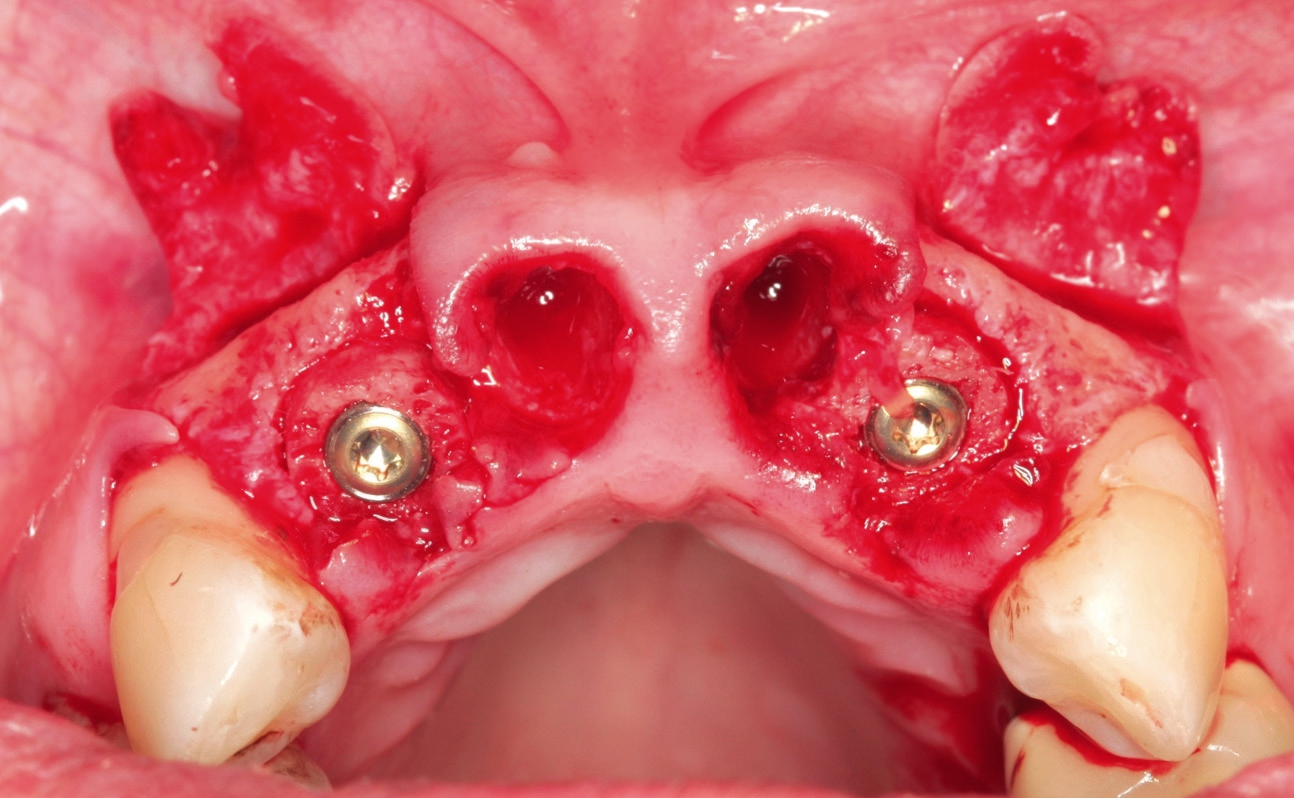

Nach Extraktion aller vier Schneidezähne (Abb. 2 und 3) zeigte sich ein massiver Knochendefekt mit Verlust der bukkalen Wand (Abb. 4). Der Behandlungsplan sah eine Augmentation und Sofortimplantation mittels Knochenringtechnik der Zähne 12 und 22 vor. Die Extraktionsalveolen der Zähne 11 und 12 sollten mit Knochen-Schleimhaut-Transplantaten aus der tuber maxillae erhalten werden, da zwischen Implantat und ovate Pontik nach Socket Preservation in der Regel eine schönere Papille zu erwarten ist.

Nach Extraktion der Zähne 12, 22, 11, 21 wurde mit dem Behandlungsprotokoll für maxgraft® bonering begonnen. Nach Pilotbohrung zur Festlegung der Implantatposition wurde mit einem 6 mm Trepan die Augmentationsstelle des maxgraft® bonerings vorbereitet (Abb. 5). Danach folgte das Planieren des Ringbettes mit einem 6 mm Planator, um ein flaches Ringbett zu generieren (Abb. 6).

Anschließend wurde das Implantatbett durch den Ring vorbereitet und ein Straumann Bone Level Tapered (BLT) Implantat ø 3,3 mm gesetzt (Abb. 7 und 8). Insgesamt erfolgte die Implantation von zwei maxgraft® bonerings 6 mm und zwei Straumann BLT Implantat ø 3,3 mm 10 mm (Abb. 9). Zur Unterstützung der Weichgewebeheilung wurde platelet-rich fibrin (PRF) aus dem Blut der Patientin gewonnen (Abb. 10). Das PRF wurde sowohl in Verbindung mit dem Knochenersatzmaterial (cerabone®) (Abb. 11), als auch als Membran über der Barrieremembran (Jason® membrane) (Abb. 12) eingesetzt. Zum Erhalt der 1er Schneidezähne wurde eine Socket Preservation mit einem Knochen-Schleimhaut-Transplantat aus der tuber maxillae durchgeführt (Abb. 14 und 15). Explantation erfolgte mithilfe eines 6er Trepans rechts und links aus dem Kieferkamm (Abb. 14).